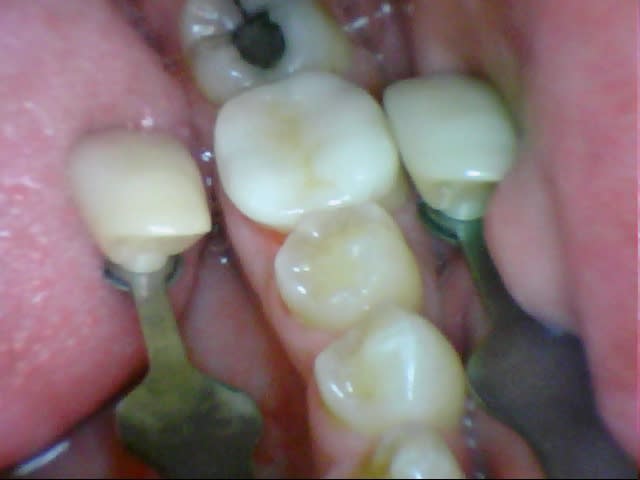

29/11/2011 à 19h22

Assez nase l'onlay Emax en couleur (B2.5 demandée, les deux teintes à côté B2 et B3), en sculpture mais là je suis responsable, j'aurais dû ménager plus de place.

J'ai etché silané mais aurais-je dû ? J'ai pris du G-Cem, j'ignore si c'est aussi efficace qu'en collage classique.

J'ai posé une digue sur la seule dent, erreur car avec l'épaisseur de la feuille, ça passe plus en proximal, donc j'ai maintenu l'élément encollé au pouce, retiré tout le tintouin en vitesse et retrouvé un torrent salivaire menaçant.

À la réflexion à froid j'aurais dû donner deux coups de ciseau/scalpel sur la digue en proximal, ç'aurait été mieux en dépannage.

Je ne sais pas encore quelle compo auto prendre pour les collages, la teinte a probablement été altérée par le G-Cem. Il y a le classique Variolink pratique avec ses seringues à produit hydrosoluble pour essai esthétique mais est-ce le meilleur produit ?

Il n'y aurait pas eu une languette profonde en distal j'aurais pris un compo photo et insolé au travers de l'onlay.